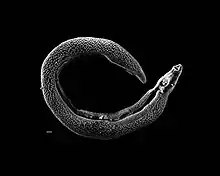

| Schistosoma | |

Schistosoma is a genus of trematodes, commonly known as blood flukes. They are parasitic flatworms responsible for a highly significant group of infections in humans termed schistosomiasis, which is considered by the World Health Organization as the second-most socioeconomically devastating parasitic disease (after malaria), with hundreds of millions infected worldwide.[1][2]

Adult flatworms parasitize blood capillaries of either the mesenteries or plexus of the bladder, depending on the infecting species. They are unique among trematodes and any other flatworms in that they are dioecious with distinct sexual dimorphism between male and female. Thousands of eggs are released and reach either the bladder or the intestine (according to the infecting species), and these are then excreted in urine or feces to fresh water. Larvae must then pass through an intermediate snail host, before the next larval stage of the parasite emerges that can infect a new mammalian host by directly penetrating the skin.

Morphology

Adult schistosomes share all the fundamental features of the digenea. They have a basic bilateral symmetry, oral and ventral suckers, a body covering of a syncytial tegument, a blind-ending digestive system consisting of mouth, esophagus and bifurcated caeca; the area between the tegument and alimentary canal filled with a loose network of mesoderm cells, and an excretory or osmoregulatory system based on flame cells. Adult worms tend to be 10–20 mm (0.39–0.79 in) long and use globins from their hosts' hemoglobin for their own circulatory system.

Reproduction

Unlike other trematodes and basically all other flatworms, the schistosomes are dioecious, i.e., the sexes are separate. The two sexes display a strong degree of sexual dimorphism, and the male is considerably larger than the female. The male surrounds the female and encloses her within his gynacophoric canal for the entire adult lives of the worms. As the male feeds on the host's blood, he passes some of it to the female. The male also passes on chemicals which complete the female's development, whereupon they will reproduce sexually. Although rare, sometimes mated schistosomes will "divorce", wherein the female will leave the male for another male. The exact reason is not understood, although it is thought that females will leave their partners to mate with more genetically distant males. Such a biological mechanism would serve to decrease inbreeding, and may be a factor behind the unusually high genetic diversity of schistosomes.[31]